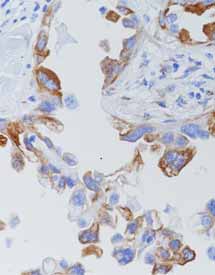

产品名称:VEGF

产品编号:RAB-0157

阳性部位:细胞质

图片描述:

血管肉瘤,VEGF染色,细胞质阳性。